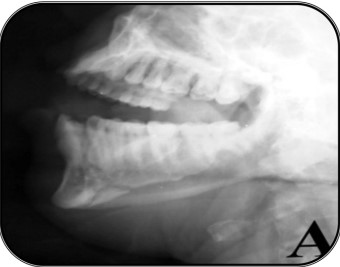

Extra-oral MultiDirectional Distractor: A Multi Uses Distractor1